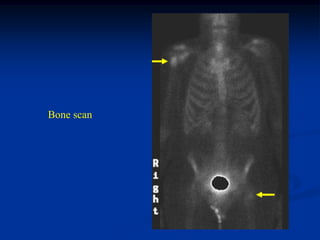

Case #573

18 year male

Ollier’s pelvis

and ribs